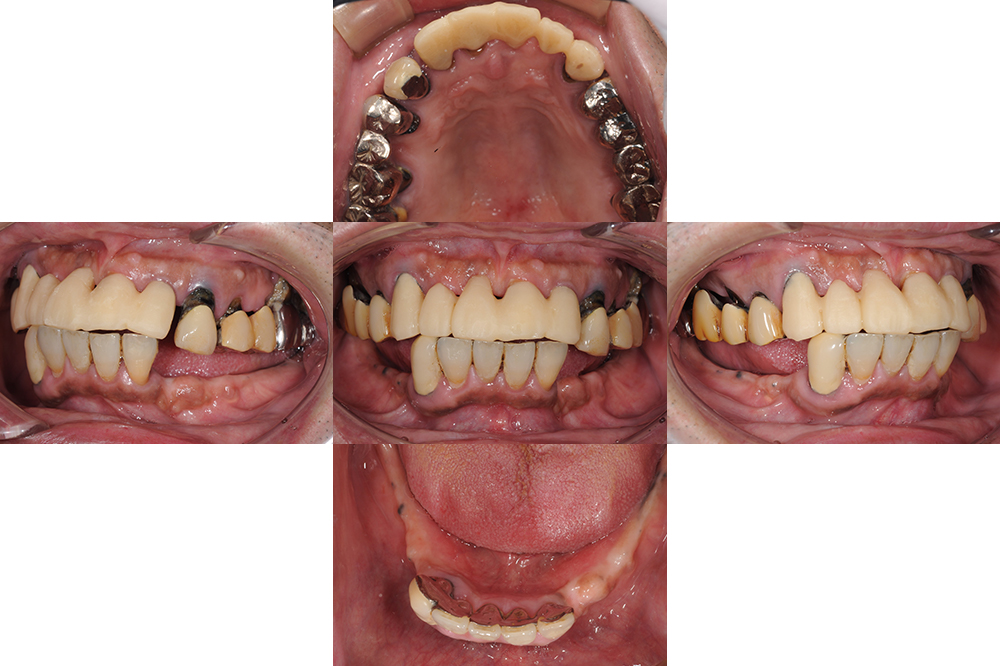

年齢 59歳 性別 女性 初診日 2021年5月 主訴 虫歯治療 治療内容 セラミック修復・ダイレクトボンディング 治療期間 1年8ヶ月 治療費用 約250万円 治療経過 右上の歯牙が破折したことを主訴に来院された。 不良な修復物も多く、歯周病も中等度に進行していた…